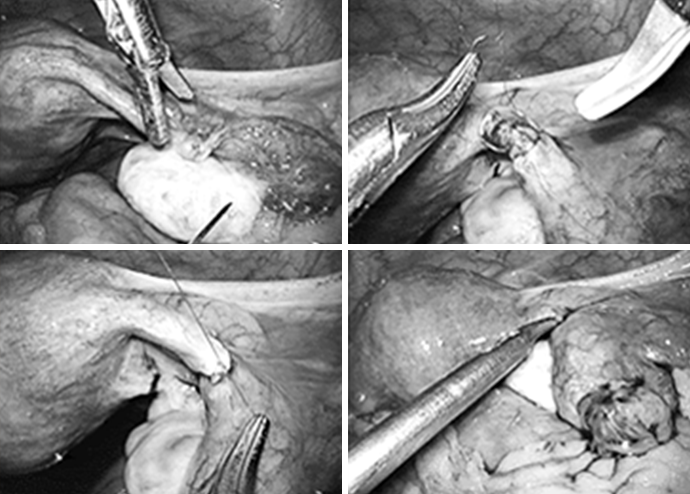

자궁근종절제술

자궁근종의 위치에 따라 근종에 의한 자궁각부분의 폐쇄나 비정상적인 자궁 수축에 의해 난자나 정자의 이동 및 배아의 착상을 방해함으로써 난임의 원인이 될 수 있습니다. 하지만 자궁근종의 크기가 너무 크거나 개수가 많은 경우엔 개복 수술을 시행할 수 있습니다.

과거에 피임 목적으로 양측 나팔관 결찰술을 시행 받은 여성이 임신을 다시 원할 때 복강경하 미세 수술로 난관이 결찰된 부위를 절제하고 난관을 다시 문합해 난관의 기능을 회복시켜 주는 수술입니다.

미세한 봉합사를 사용하고 복강 내에서 난관의 여러 층을 정확하게 문합 해야 하기 때문에 복강경 술기 중에서도 가장 고도의 수술 능력을 요구하는 수술입니다. 차병원 여성의학연구소는 전세계적으로 가장 많은 난임 관련 수술 경험과 임신 성공율을 보여주고 있습니다.